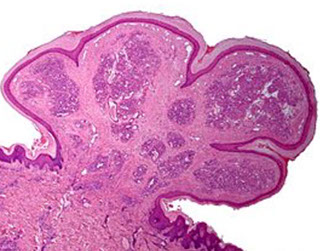

Keratoacanthoma

Could be derived from infundibular part of hair follicle, or possibly a subtype of well-diff SCC

- 4/5 Males, usually on face, which grows quickly over about 2 months, then spontaneously regresses (slowly) over 6 months, leaving a depressed scar behind

Early - well circumscribed solid lobules of large pale sq cells c little keratinization; mild atypia and distorted follicular infundubuum

Stable - central keratin plug but no granular layer;

- also larger and more atypical squamous nests and islands c lots of lichenoid inflam and eos but no plasma cells; possible neutros microabscesses

Regressing (resolving) - keratin filled crater, mature epithelium without atypia; flattening cup-shaped dermis

- not as much inflam as previous stage